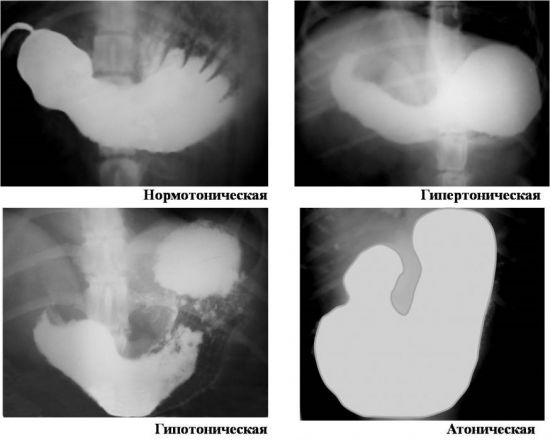

Зміст Де знаходиться шлунок? Розміри і форма Органи-сусіди Відділи і їх анатомія Будова стінки шлунка